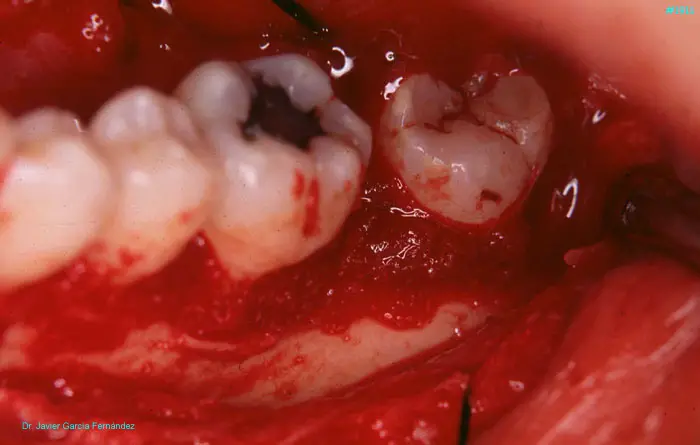

image 58